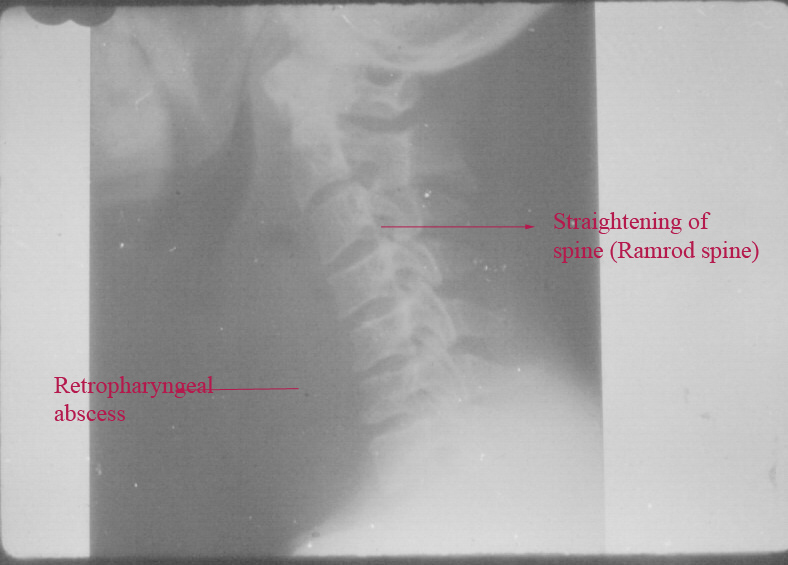

Xray soft tissue neck - A.P. and lateral views.

These pictures show prevertebral soft tissue widening. This can be ascertained by estimating the size of the prevertebral soft tissue which is normally half the size of the body of the corresponding vertebra. If the widening is more than half the body size of the corresponding vertebra then retropharyngeal abscess must be considered. The cervical spine are straightend with loss of the normal lordosis (Ram Rod spine). Above the prevertebral shadow air shadow is seen in almost all cases of retropharyngeal abscesses. This gas shadow is caused by entrapped air which occur during breathing. Some bacteria esp. Clostridium are known to form gases which may be entrapped in the prevertebral space.

X-ray soft tissue neck lateral view showing features of retropharyngeal abscess